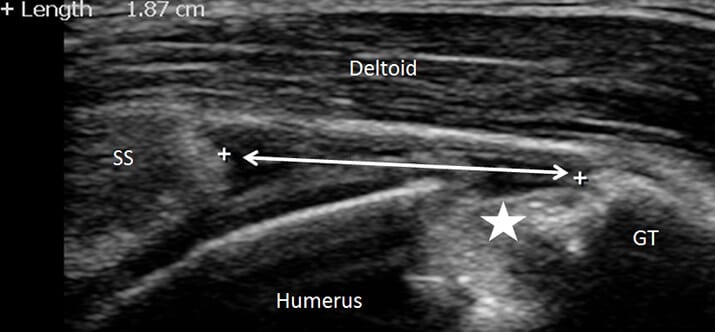

A ultrassonografia musculoesquelética é considerada o padrão-ouro para avaliação inicial de distúrbios do tendão, como a síndrome do manguito rotador. Além disso, entre as principais vantagens do método estão a facilidade de utilização, a ausência de radiação e o custo relativamente acessível.

No diagnóstico por ultrassom para a síndrome do manguito rotador, as alterações podem incluir:

Realização do exame de ultrassom

A visualização adequada dos tendões exige um bom posicionamento do paciente (posição de Crass) e do transdutor, ajustes corretos no equipamento de ultrassom e manobras dinâmicas para obter as melhores imagens.

Para a maioria dos casos, utiliza-se um transdutor linear com frequência de 10 MHz e zona focal de cerca de 2 cm de profundidade.

A posição de Crass ideal, por sua vez, pode ser difícil em pacientes com dor, mas é possível facilitar a manutenção dessa posição pedindo ao paciente para simular o ato de pegar uma carteira no bolso de trás e sentar-se sobre a mão, utilizando o peso corporal.

Após posicionar corretamente o transdutor, o examinador pode realizar ajustes adequados na posição para melhorar a visualização do tendão e avaliar a anisotropia.